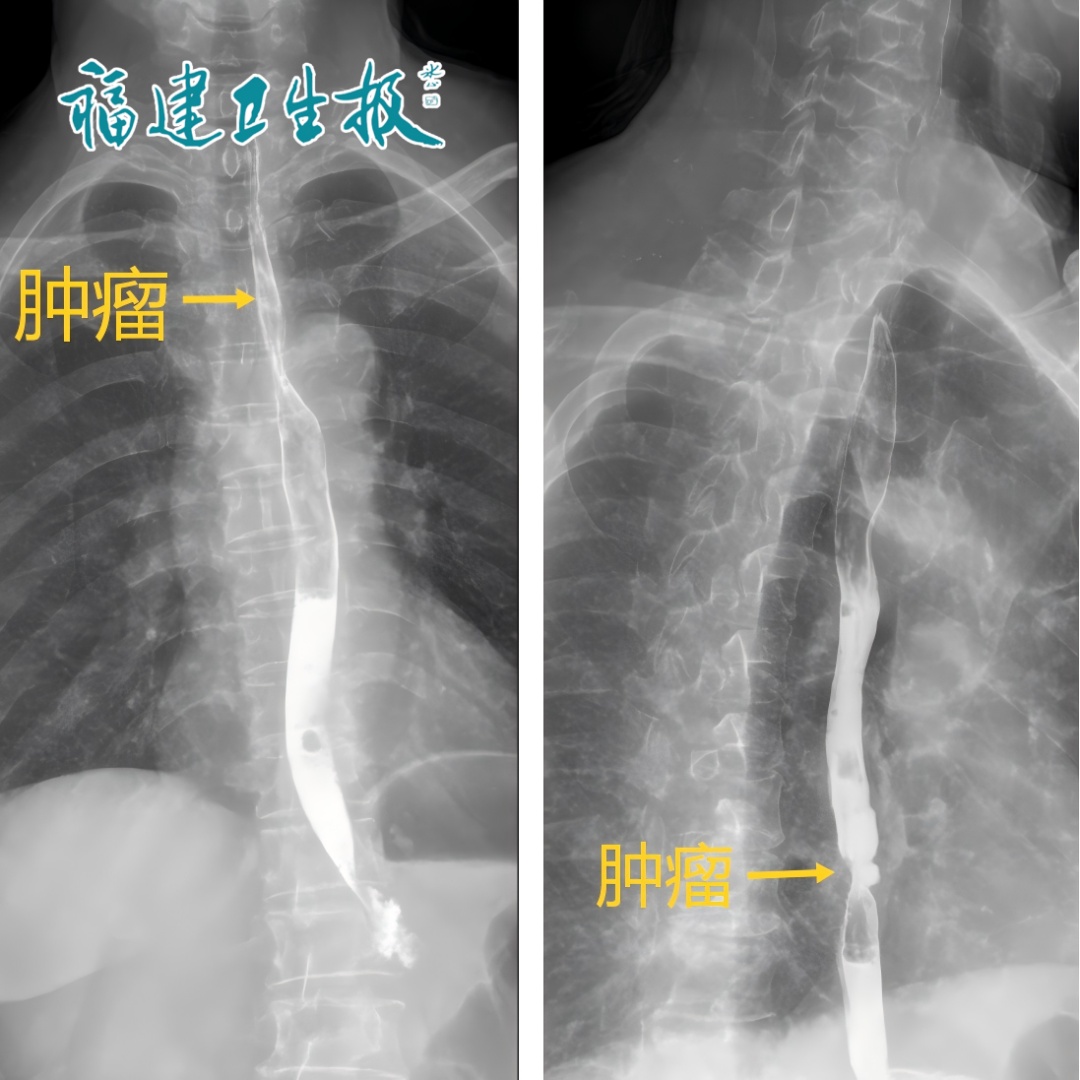

今年1月,泉州56岁的徐先生(化名)和妻子前往当地的医院体检。没想到,做胃肠镜时,夫妻俩都被查出了食管癌。幸运的是,夫妻俩发现及时,没有转移,尚属于早期。

▲夫妻俩都发现食管癌